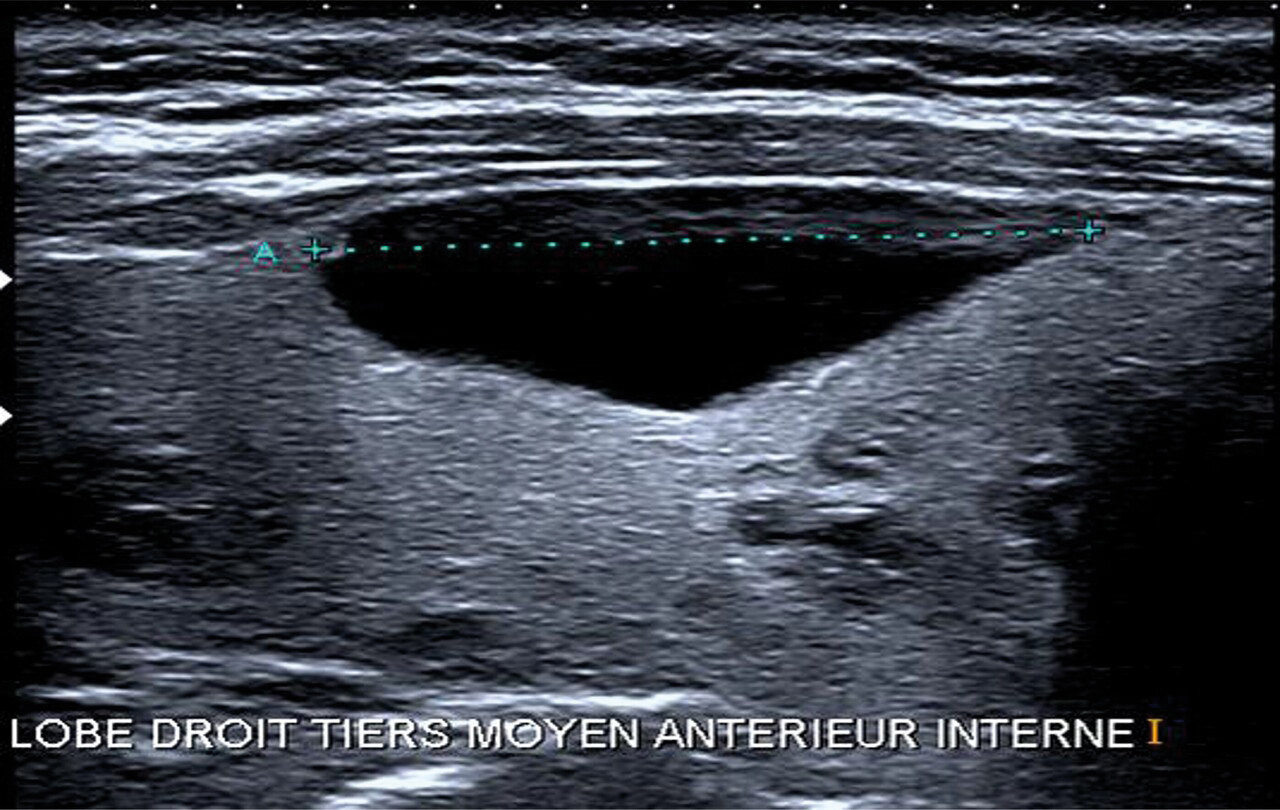

Le nodule peut être découvert à la palpation cervicale par le patient ou son médecin (40 à 50 % des cas), mais, de plus en plus souvent (30 à 40 % des cas),5 il s’agit d’une découverte fortuite lors d’un examen d’imagerie (échographie, scanner [fig. 1], scintigraphie, tomographie par émission de positons [TEP]). Une dysthyroïdie est révélatrice dans 10 à 15 % des cas. Le motif de consultation peut être une gêne fonctionnelle : dysphagie, gêne à la déglutition, dysphonie (si atteinte du nerf récurrent), dyspnée (si compression trachéale) qui peut faire découvrir un goitre thyroïdien (fig. 2). Des signes d’hyperthyroïdie doivent bien évidemment attirer l’attention (nodule toxique, maladie de Basedow).

L’échographie thyroïdienne et cervicale est un examen systématique qui fournit des informations essentielles à la suite de la prise en charge : volume de chaque lobe thyroïdien, taille des nodules, classification européenne du système d’imagerie et de données sur la thyroïde (EU-TIRADS)6 et présence d’adénopathie cervicale. La classification radiologique EU-TIRADS évalue le risque de malignité d’un nodule de 2 (fig. 4) à 5 (tableau 1).